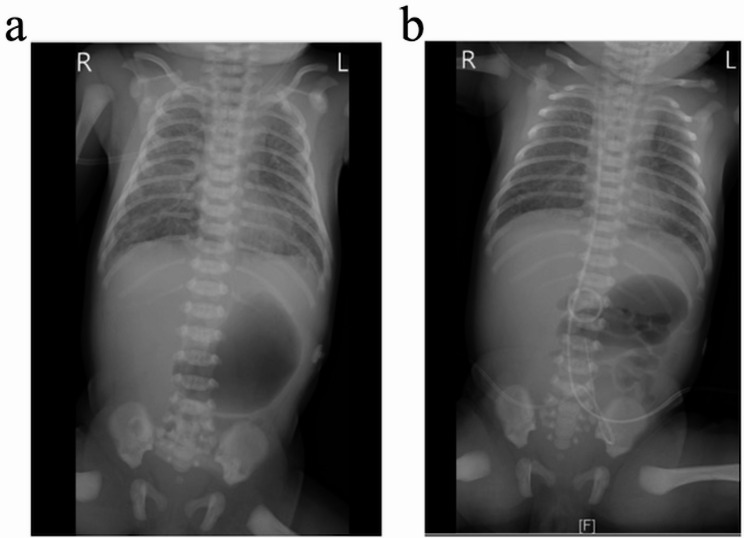

Case presentation: This is a full-term female neonate born to a healthy mother via cesarean section due to suspected fetal distress with meconium-stained amniotic fluid. She required resuscitation in the delivery room and was subsequently admitted to the neonatal intensive care unit for respiratory distress. Both the mother and the baby exhibited fever after delivery, and cultures from the baby's blood and amniotic fluid revealed the same strain of SGSP. The baby had MAS and developed severe pulmonary hypertension, which was successfully treated with a comprehensive approach that included ampicillin, high-frequency oscillatory ventilation, inhaled nitric oxide, fluid resuscitation, and vasopressors. A significant increase in the white blood cell count was noted during her clinical improvement, followed by a spontaneous decline. The baby completed a 12-day course of ampicillin and was followed up to 1 year of age, during which she thrived. A systematic literature review on early-onset SGSP sepsis was also conducted.